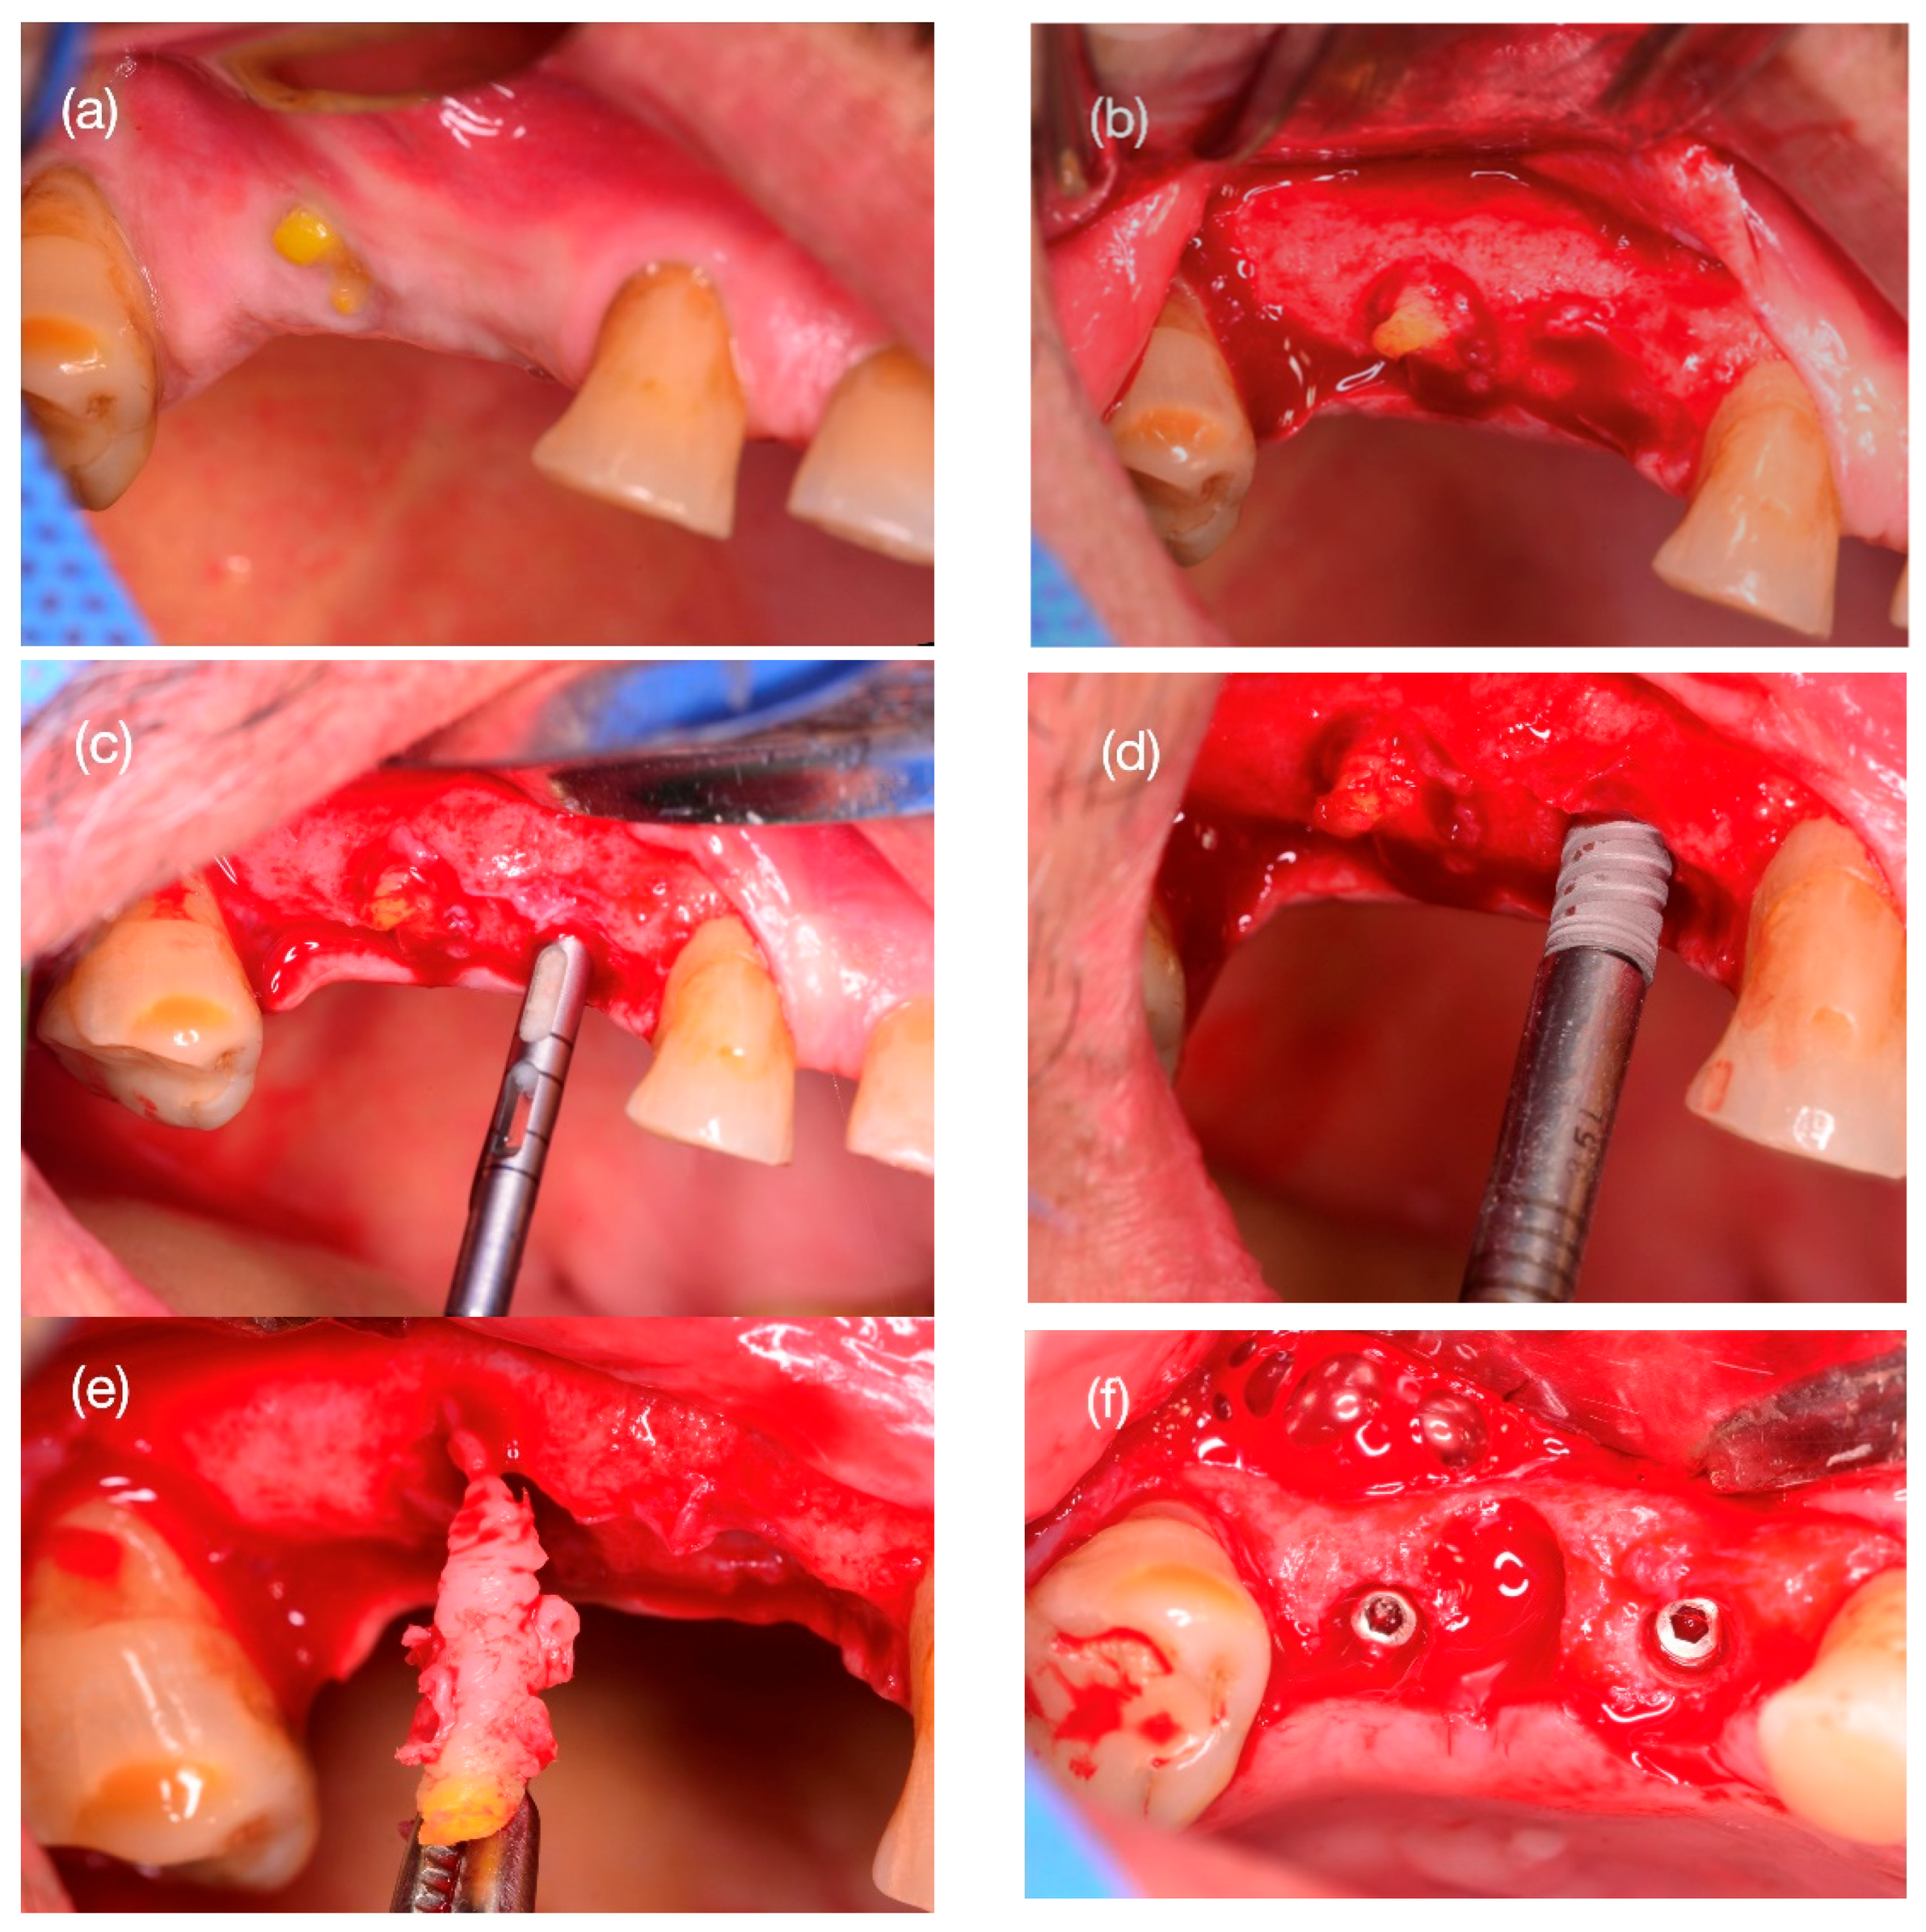

2.4. Step 1: Surgery Tooth Extraction and Scaffold Placement